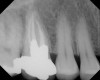

Figure 5  Retreatment of the case shown in Figure 4.

Figure 5